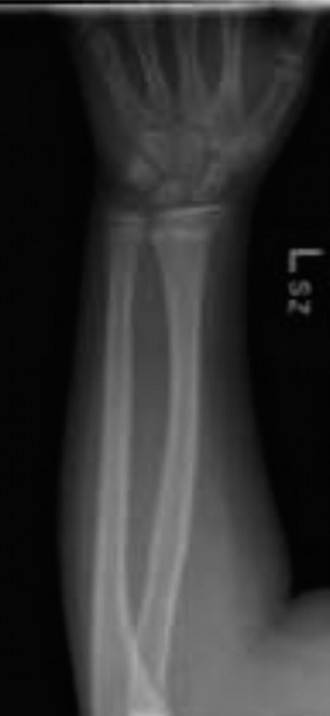

The intra-operative posteroanterior fluoroscopic view demonstrated excellent restoration of the radial length and correction of the coronal plane alignment. The fracture fragments appeared anatomically apposed.

The intra-operative lateral fluoroscopic view confirmed successful reduction of the dorsal displacement and complete correction of the apex volar angulation. The volar cortical continuity was restored, and the dorsal periosteal hinge appeared to be holding the reduction in an anatomical position.

Percutaneous Pinning Construct

Despite the excellent fluoroscopic appearance of the closed reduction, the initial displacement parameters (75% translation) indicated a highly unstable fracture pattern. To prevent secondary loss of reduction, percutaneous pinning was performed.

Clinical & Radiographic Imaging